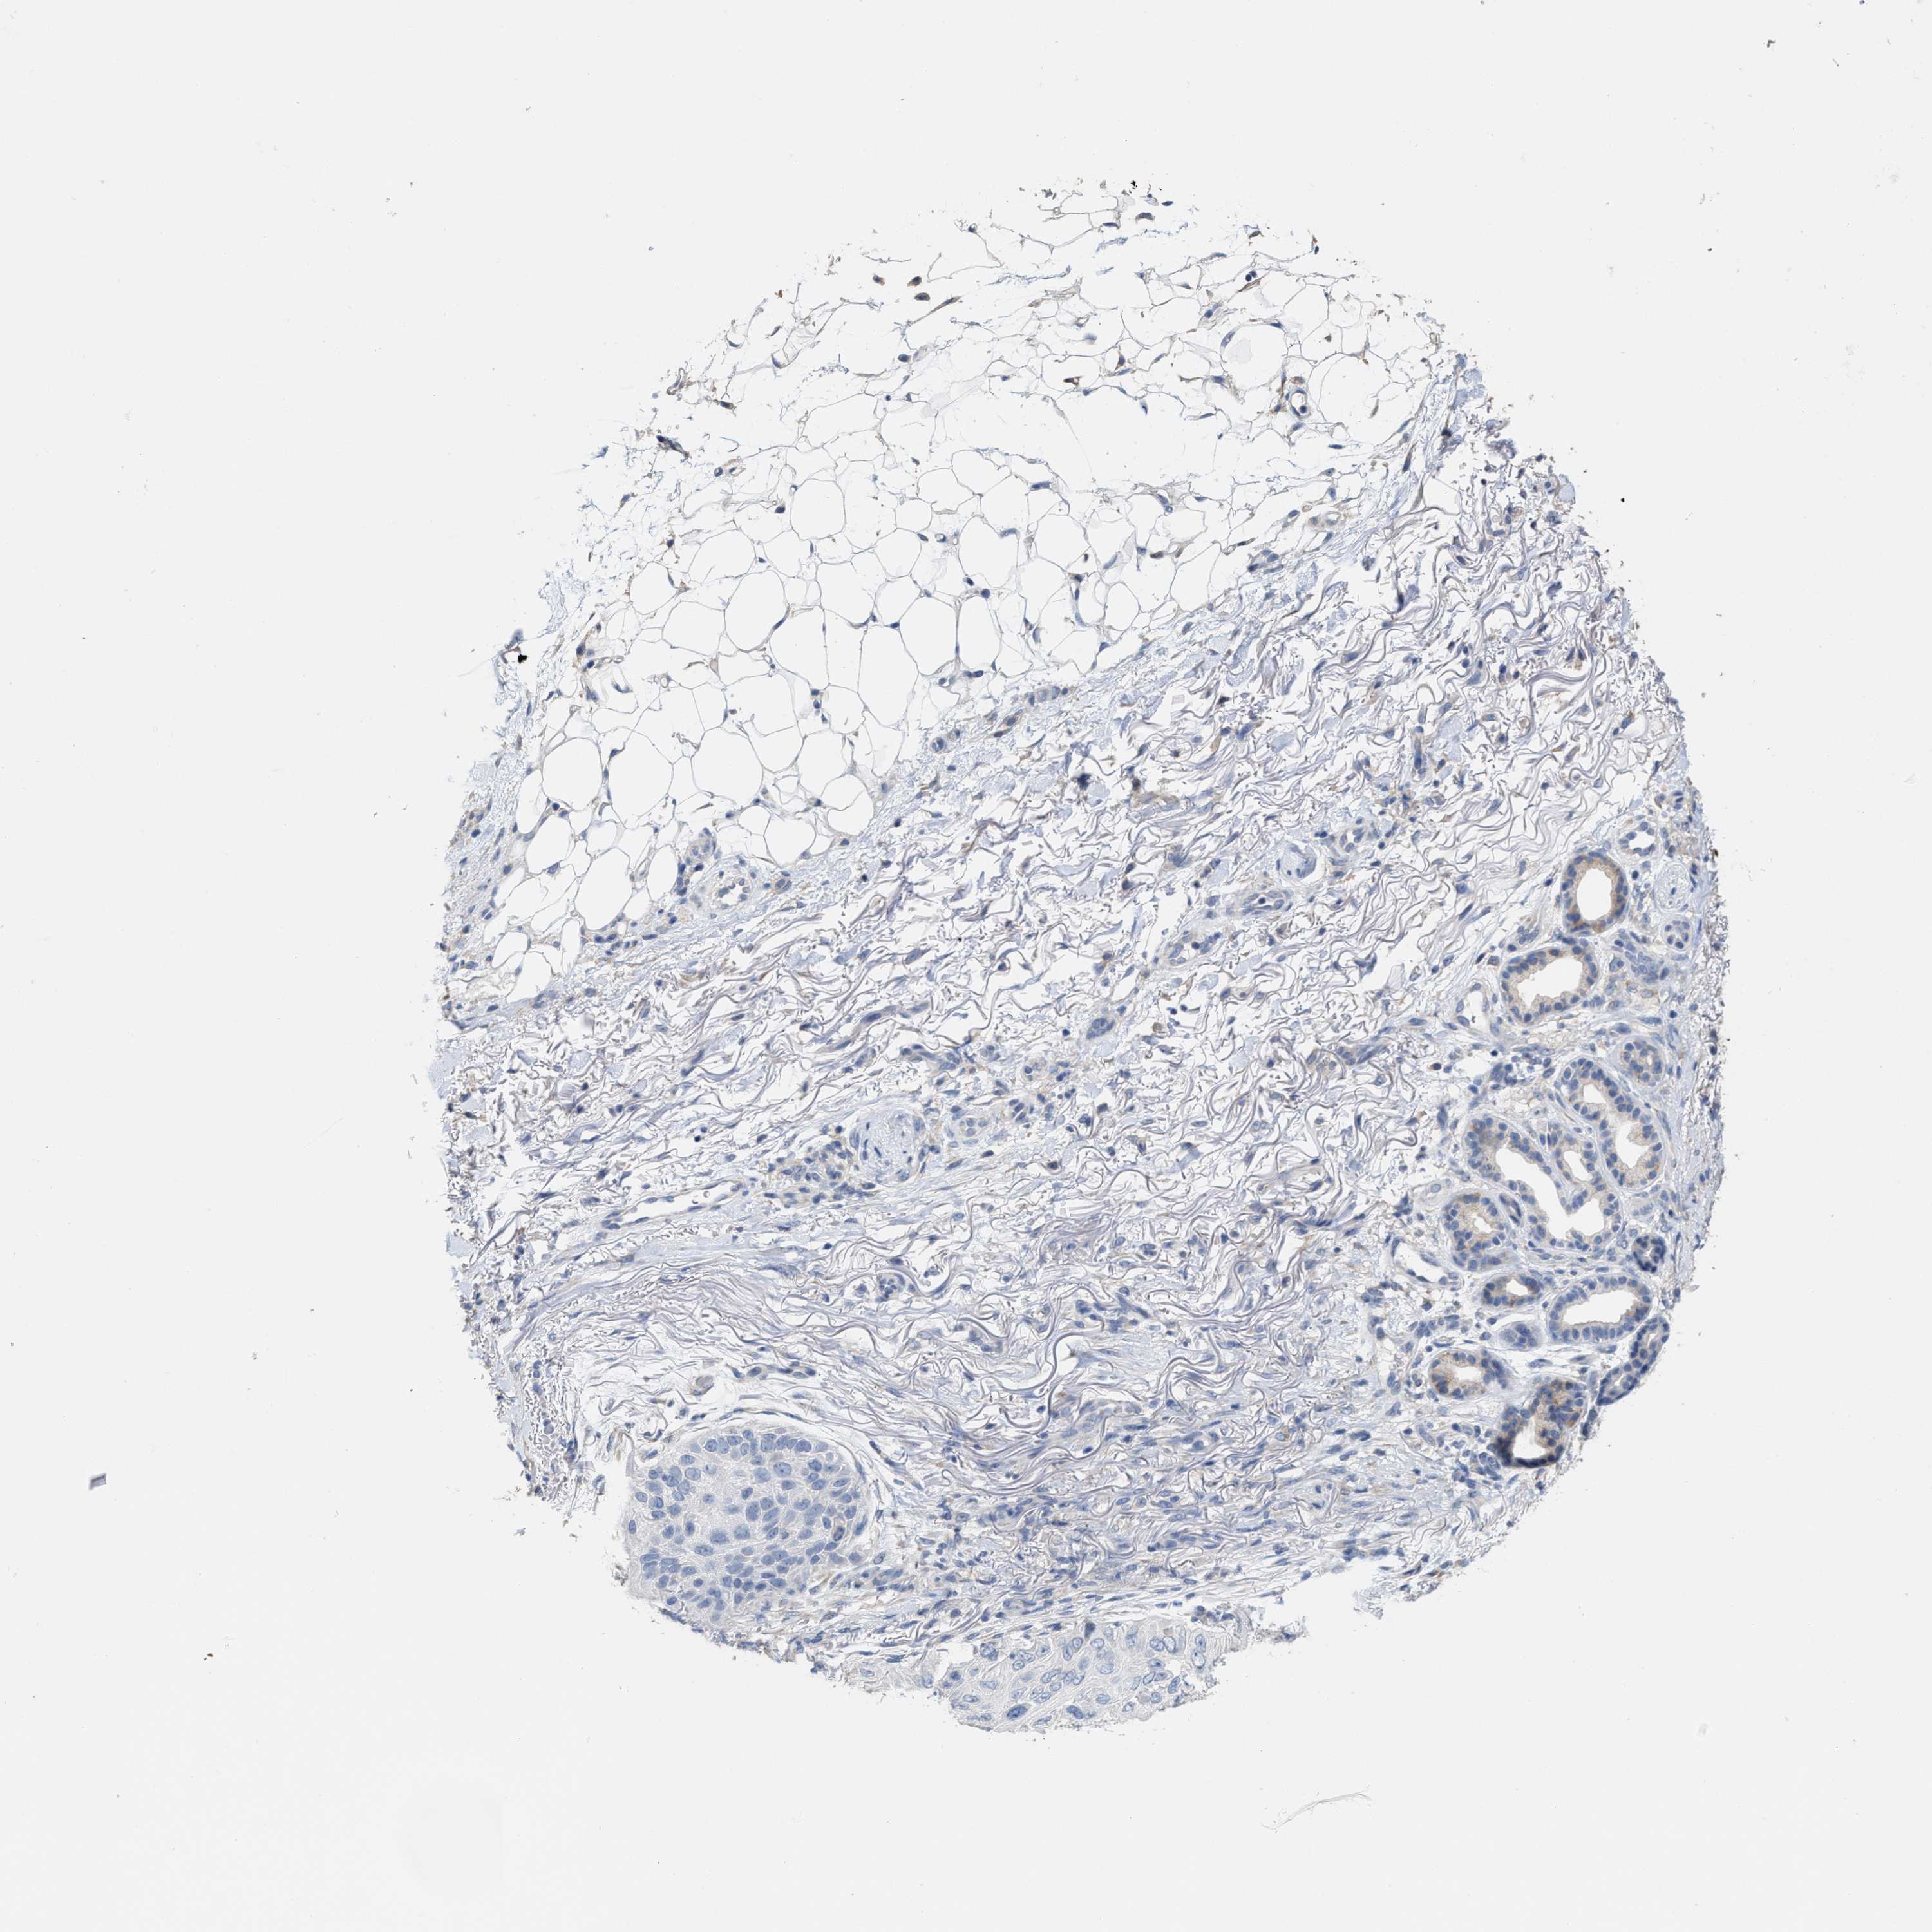

Basal cell and squamous cell cancer

SKIN CANCER - Protein expressioni

A mouse-over function shows sample information and annotation data. Click on an image to view it in a full screen mode. Samples can be filtered based on level of antibody staining by selecting one or several of the following categories: high, medium, low and not detected. The assay and annotation is described here.

Antibody stainingi

Antibody staining in the annotated cell types in the current human tissue is reported as not detected, low, medium, or high, based on conventional immunohistochemistry profiling in selected tissues. This score is based on the combination of the staining intensity and fraction of stained cells.

Each image is clickable and will lead to virtual microscopy that enables deeper exploration of all samples and also displays staining intensity scores, fraction scores and subcellular localization as well as patient and tissue information for each sample.

Antibody HPA020028

Staining

High

Medium

Low

Not detected

Intensity

Strong

Moderate

Weak

Negative

Quantity

>75%

75%-25%

<25%

None

Location

Nuclear

Cytoplasmic/membranous

Cytoplasmic/membranous,nuclear

Basal cell carcinoma

Squamous cell carcinoma, NOS

Squamous cell carcinoma, metastatic, NOS